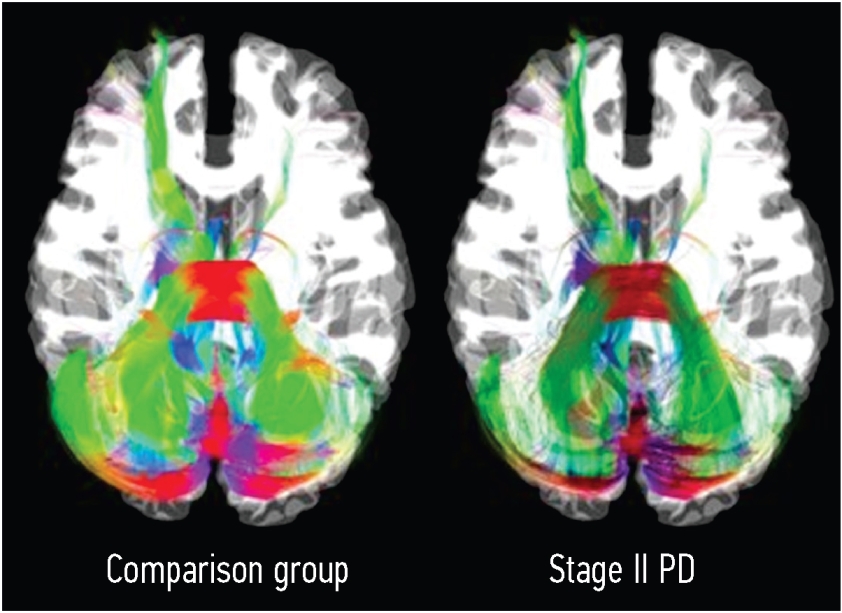

Patients with PD showed a significant decrease in the FA of the rubrospinal tract, medial longitudinal fasciculus, and inferior cerebellar peduncle on the right side (Figures 1–3).

Fig. 1. Visual comparison of the right inferior cerebellar peduncle between the controls and patients with stage II Parkinson’s disease (PD) using the Hoehn and Yahr scale

Fig. 2. Visual comparison of the right rubrospinal tract between the controls and patients with stage II Parkinson’s disease (PD) using the Hoehn and Yahr scale

Fig. 3. Visual comparison of the right medial longitudinal fascicle between the controls and patients with stage II Parkinson’s disease (PD) using the Hoehn and Yahr scale

In addition to the gray matter, modifications affect the neuronal pathways of the brain. Patients diagnosed with stage II PD showed FA reduction in the rubrospinal tract, medial longitudinal bundle, and inferior cerebellar peduncle on the right.